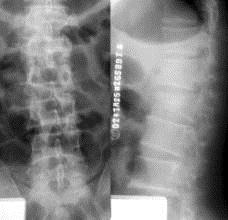

病历摘要: 患者×××,男性,21岁,不慎从3米高处坠落,双足着地,出现双足跟肿胀疼痛,腰痛不能站立。查体:腰1棘突有压痛和叩击痛,双足足跟部肿胀,触痛(...

问题 病历摘要: 患者×××,男性,21岁,不慎从3米高处坠落,双足着地,出现双足跟肿胀疼痛,腰痛不能站立。查体:腰1棘突有压痛和叩击痛,双足足跟部肿胀,触痛(+),双下肢感觉正常,双足伸足母、伸趾正常,双膝关节伸屈正常。 关于胸腰椎骨折脊髓手术探查的适应症,以下叙述正确的是?